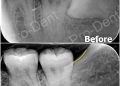

止鼾案例-配戴前